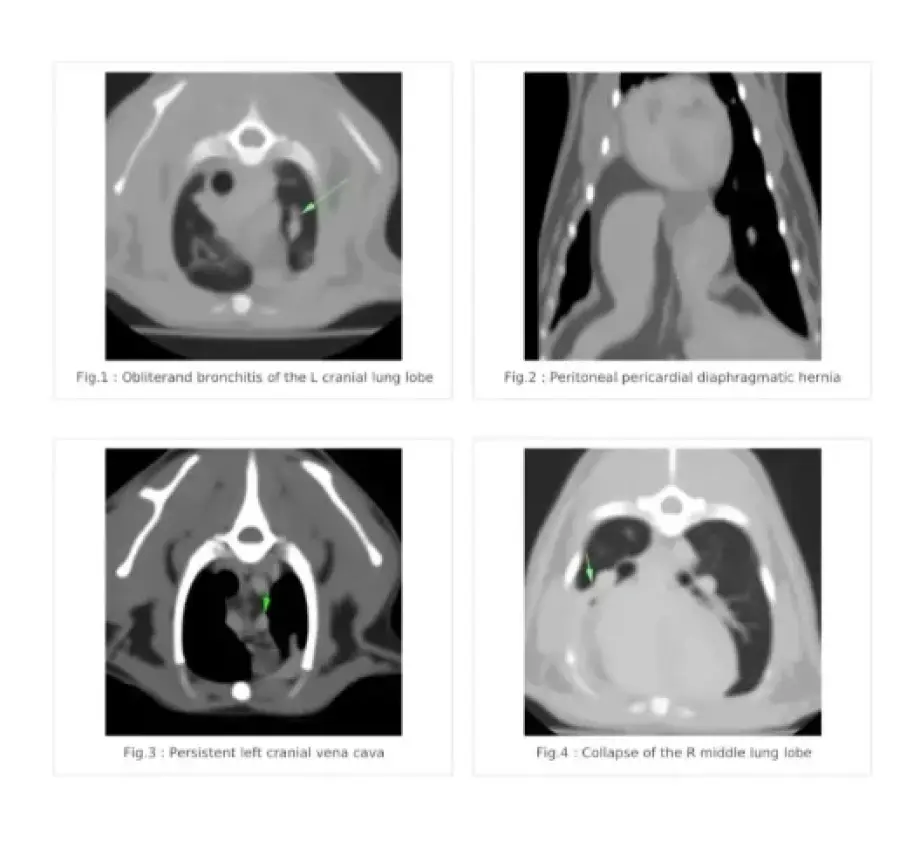

Хочу поделится своей историей покупки взрослой кошечки породы Девон рекс у заводчицы Zainaba Balabaja из питомника «Bambielf Mystery», которая в итоге оказалась больная, с врожденной деформацией диофрагмы, сросшимися органами, сжатым правым легким и еще кучей других проблем. Питомник зарегистрирован на имя её дочери Ирины Скобовы в Саласпилсе, по факту заводчица проживает и разводит котят в плявниеках. Если вкратце, весной 16го марта я приобрела у заводчицы кошечку породы Девон Рекс 4х лет, которая использовалась для разведения котят. Я и мой молодой человек созвонились с заводчицей и приехали к ней в скором времени посмотреть кошечку. В квартиру она нас не пустила, аргументируя тем что она и её муж возрастные, переболели ковидом и никого не пускают, а я наивная во все это поверила, так как это был мой первый опыт с заводчиками. Кошечку вывели на лестничную клетку в переноске, визуально она выглядела здоровой. Мы договорились об оплате наличными в размере 450 евро, о перерегистрации паспорта на меня и стерилизации через месяц в рекомендованной ей клинике, так как кошке недавно делали прививку. Договор и родословную она мне не выдала. Когда я забирала паспорт, она сказала что родословная нужна в том случае если я собираюсь водить кошку на выставки, и я решила не платить за перерегистрацию родословной на меня, так как не планировала кошку ни разводить, ни участвовать в выставках. Когда кошка начала жить у меня, спустя некоторое время у нее начали слезится глаза, заводчица уверяла что это из-за прививки. После я начала замечать что кошка часто чешется в районе подбородка и ушей, глаза все время слезились и она начала кашлять. После стерилизации кашель ухудшился, на что в клинике мне ответили что скорее всего кошка аллергик, сделали ей стероидный укол после чего симптомы прекратились на несколько недель, а потом все началось заново. На мои просьбы сделать анализы и рентген был отказ. После по совету ветов я водила кошку к вет дерматологу Евгении Кондратьевой на две консультации, были выписаны медикаменты от паразитов и курс чистки ушей, но кашель и частые чесания ушей и подбородка не прекратились. После был выписан бронхиальный ингалятор, это тоже не помогло. На мои просьбы о том, что я хотела бы сделать сразу рентген и сдать анализы был отказ, мол, надо наблюдать. В итоге в один вечер у кошки был очередной приступ кашля, который длился не минуту как обычно, а около 5-10 минут с перерывами. Я и парень повезли её в клинику Vet24, где сразу сделали рентген, взяли анализы и проверили на клещей. Какого было наше удивление когда вет принесла рентген с непонятным большим образованием давящим на органы, сказала что это не похоже на рак, но нужно делать КТ и проверить сердце. В итоге через пару дней ей сделали КТ, через месяц проверили сердце. Есть еще подозрение на проблемы с печенью, анализы на мочу показали наличие кристаллов песка. В итоге у кошки диагностировали PPDH, вкратце у кошки пока она была в эмбриональном развитии неправильно сформировалась диафрагма, образовалось отверстие и через него вышла печень и срослась с сердечной сумочкой. Органы давят на левое легкое. Правое сжатое. Сердце при этом, слава богу, пока что в порядке. Отдали мы на ветов уже больше 1000 евро, успели поменять куча кормов чтобы уменьшить симптомы аллергии и чтобы не было нагрузки на печень, переодически используем стероидный ингалятор, кошке предстоит пожизненное наблюдение у ветов, ежегодные обследования. После консультации с хирургом был сделан вывод что операцию делать смысла нет, так как с большей вероятности кошка просто умрет от потери крови. Если еще учитывать, что кошка давала потомство минимум раз в год за свои 4 года, котята давили на и так деформированные органы, а кашель заводчица просто не могла не замечать, у меня складывается подозрение что заводчица за всю жизнь кошки даже нормально ее ни разу не обследовала у вета, хотя животное ей создавало доход. Так же я нашла отзыв на sudzibas.lv за 2023 год, где мужчина приобрел двух котят у этой же заводчицы, которые оказались с клещами и хламидиозом. Жалобу я, конечно же, увидела слишком поздно. Та же схема, не пускает в квартиру посмотреть котят под предлогом ковида и уверяет что котята здоровые, а слезящиеся глазки после прививки. Сумма на ветов и обследования за пол года уже привысила 1000 евро и бог с этими деньгами на лечение, меня больше всего злит обман и абсолютное потребительское отношение к животным, которые создают тебе доход. С заводчицей после получения вет паспорта я в дальнейшем не контактировала, так как не вижу смысла выяснять отношения с человеком, который меня намеренно обманул и продал больное животное. Считаю что здесь нужно подключать соответсвующие инстанции. Скрины заключений, КТ, рентгенов прикреплю к посту. Так же сохранились скриншоты переписок с заводчицей, объявление о продаже кошки, большая часть выписок и переписок с ветами.

Прикладываю копию рентгена, результата КТ, объявление о продаже кошки, профиль заводчицы и название питомника в списке клуба Mooncat сюда в комментарии